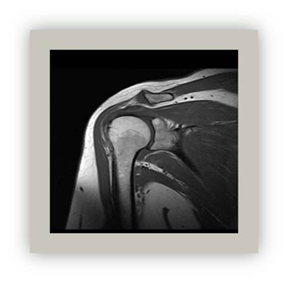

Magnetic resonance

This method based on applying radio waves to a magnetic field. It provides an important image of the central nervous system and musculoskeletal soft tissues (Figure 5 & Figure 6).28‒31

Figure 5 The shoulder MR T1 TSE coronal section.